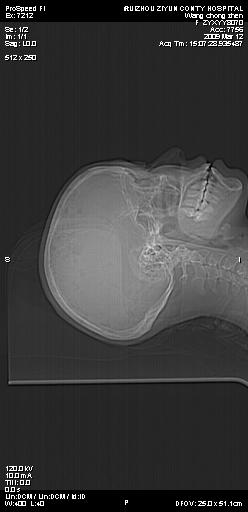

标题: CT18636:F 44Y,头痛三个月,左侧肢体麻木一周。临床诊断, [打印本页]

标题: CT18636:F 44Y,头痛三个月,左侧肢体麻木一周。临床诊断,

右额叶脑沟变浅,脑表面见新月形稍高密度影,考虑慢性硬膜下出血可能。

额顶骨多发穿凿样骨缺损区,不排除骨髓瘤等改变,进一步检查。